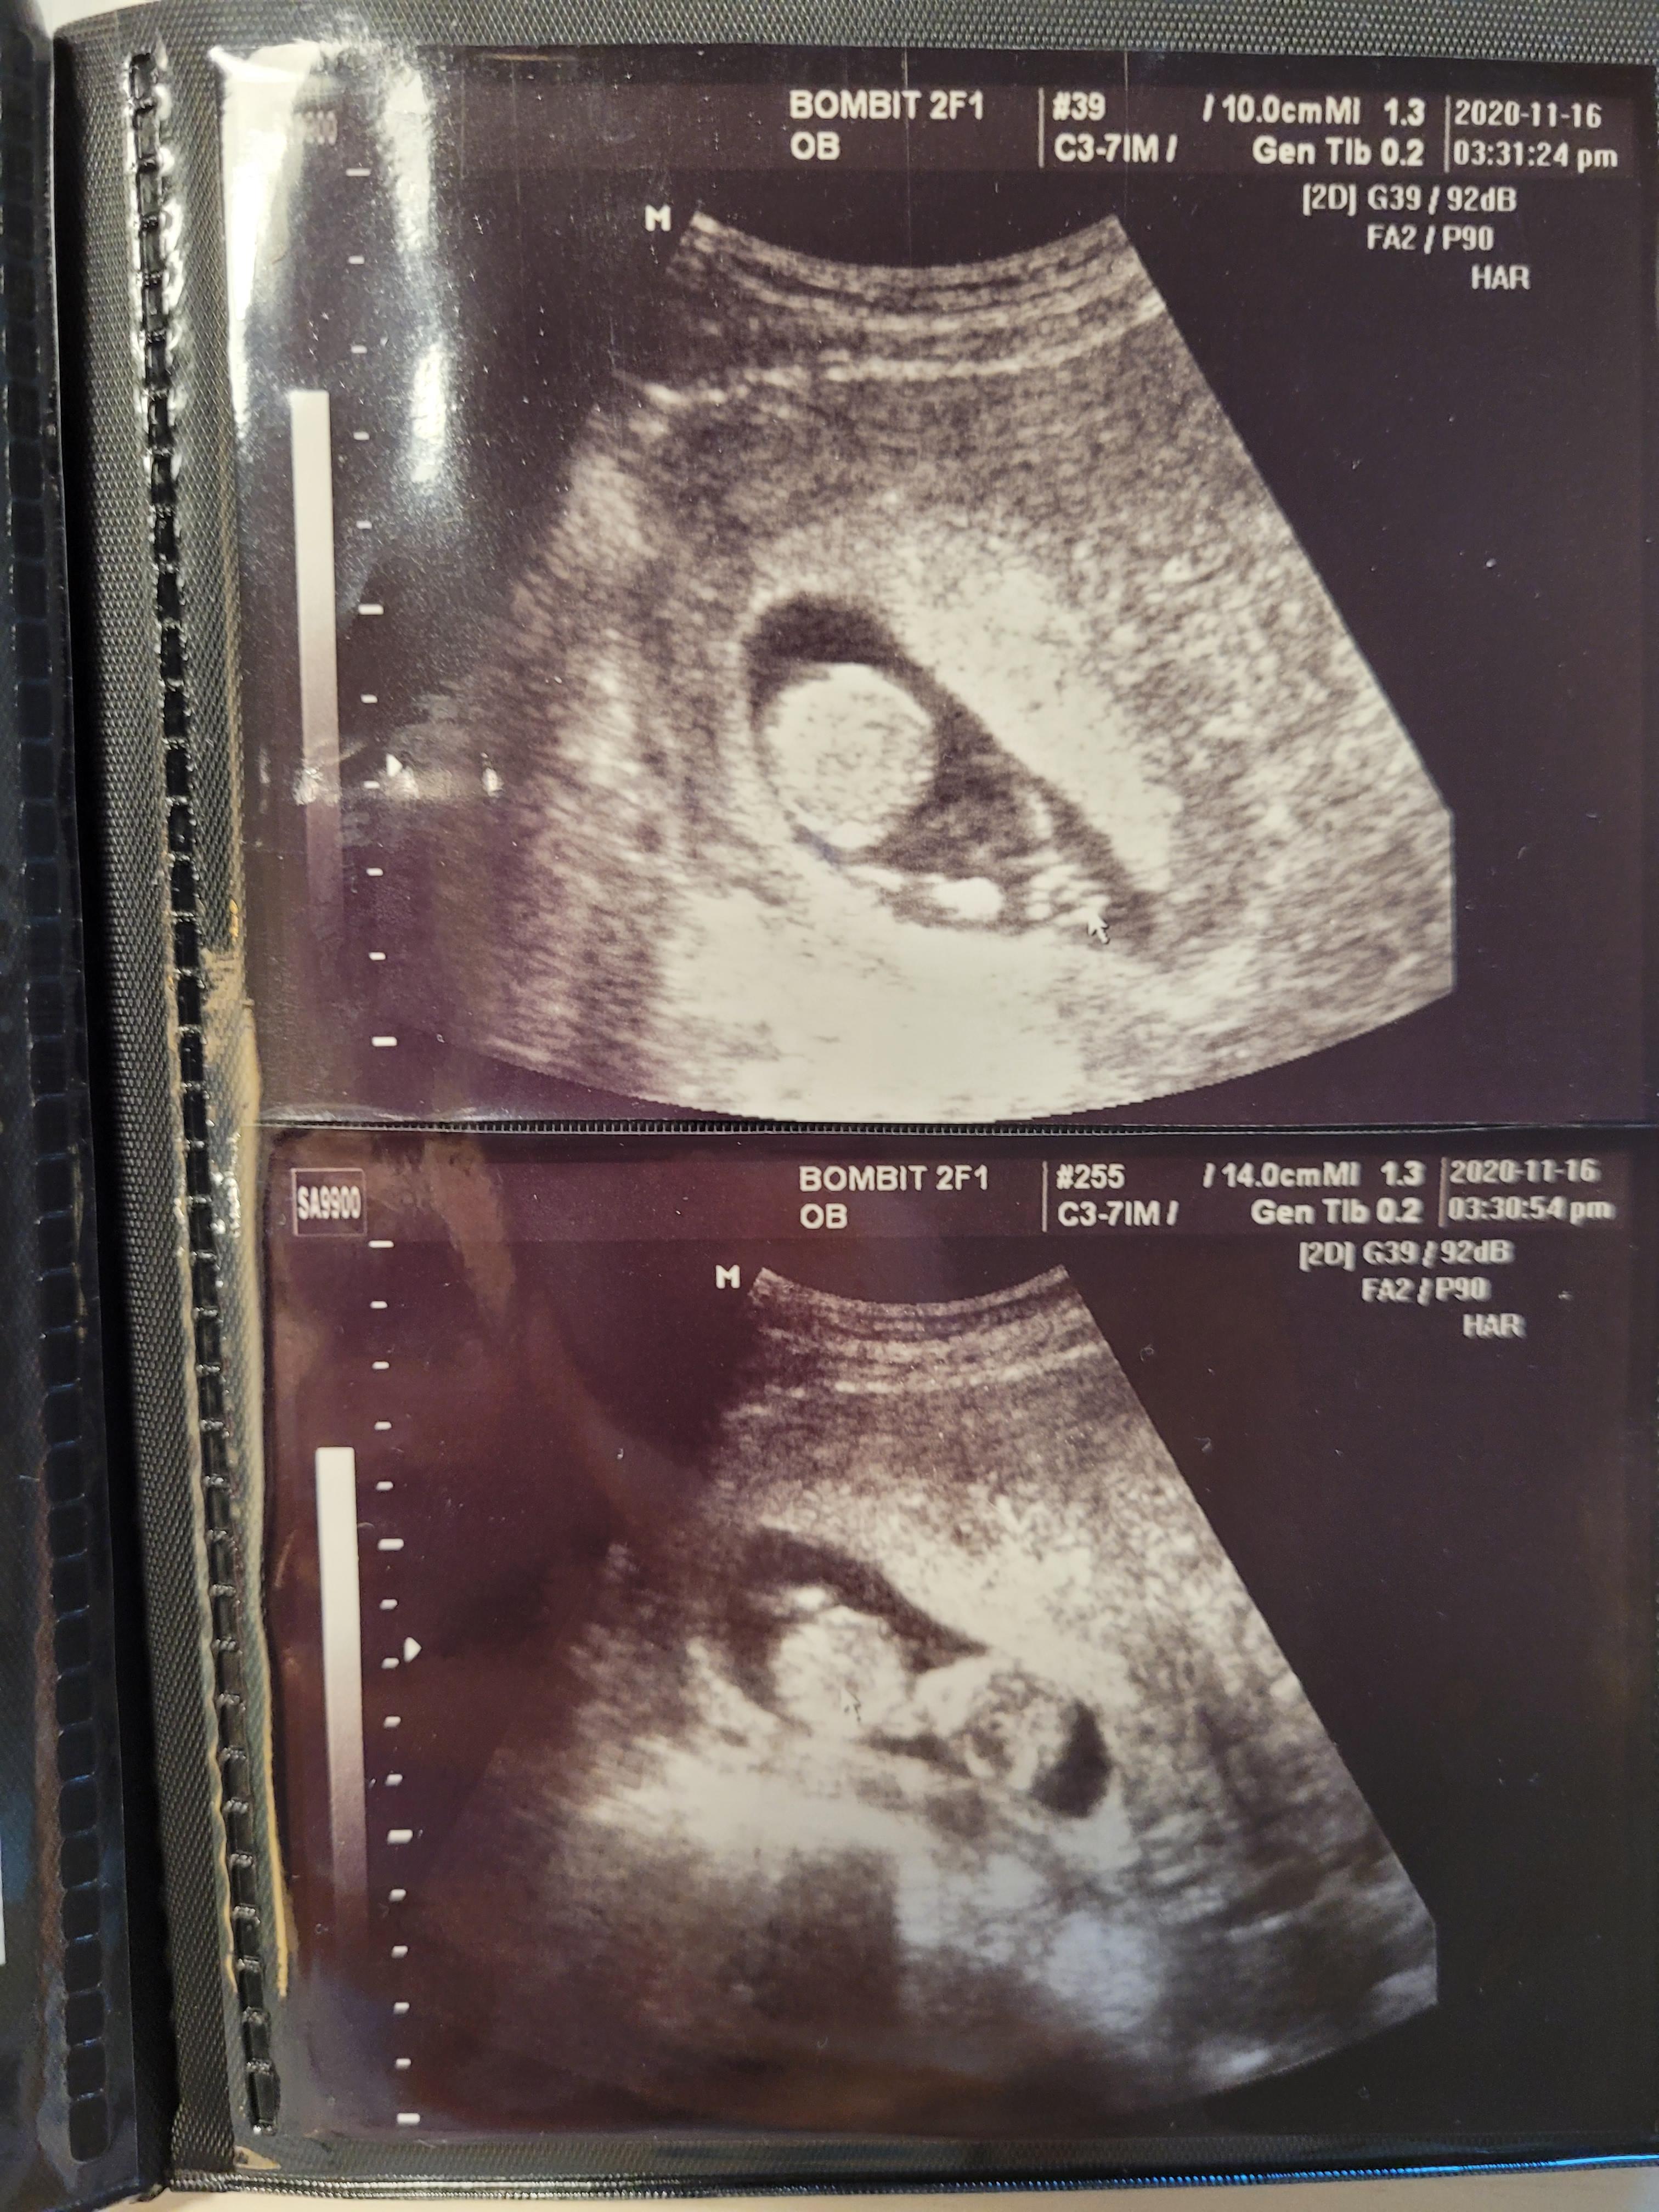

임신 중기 검사, 1차 기형아검사

이제 12주가 지나면, 임신 중기에 접어듭니다.

12주에 1차 기형아검사를 하고, 4주 뒤 2차 기형아검사를해요.

1차 기형아검사는 태아 목투명대 검사로, 초음파로 목투명대 길이를 재는 검사가 있고요.

2차 기형아검사는 초음파, 채혈, 소변검사로 진행해요.

제가 다니는 봄빛병원은 1차, 2차 검사를 모두 마친 후에 일주일이내에 종합 결과를 알려준다고 했어요.